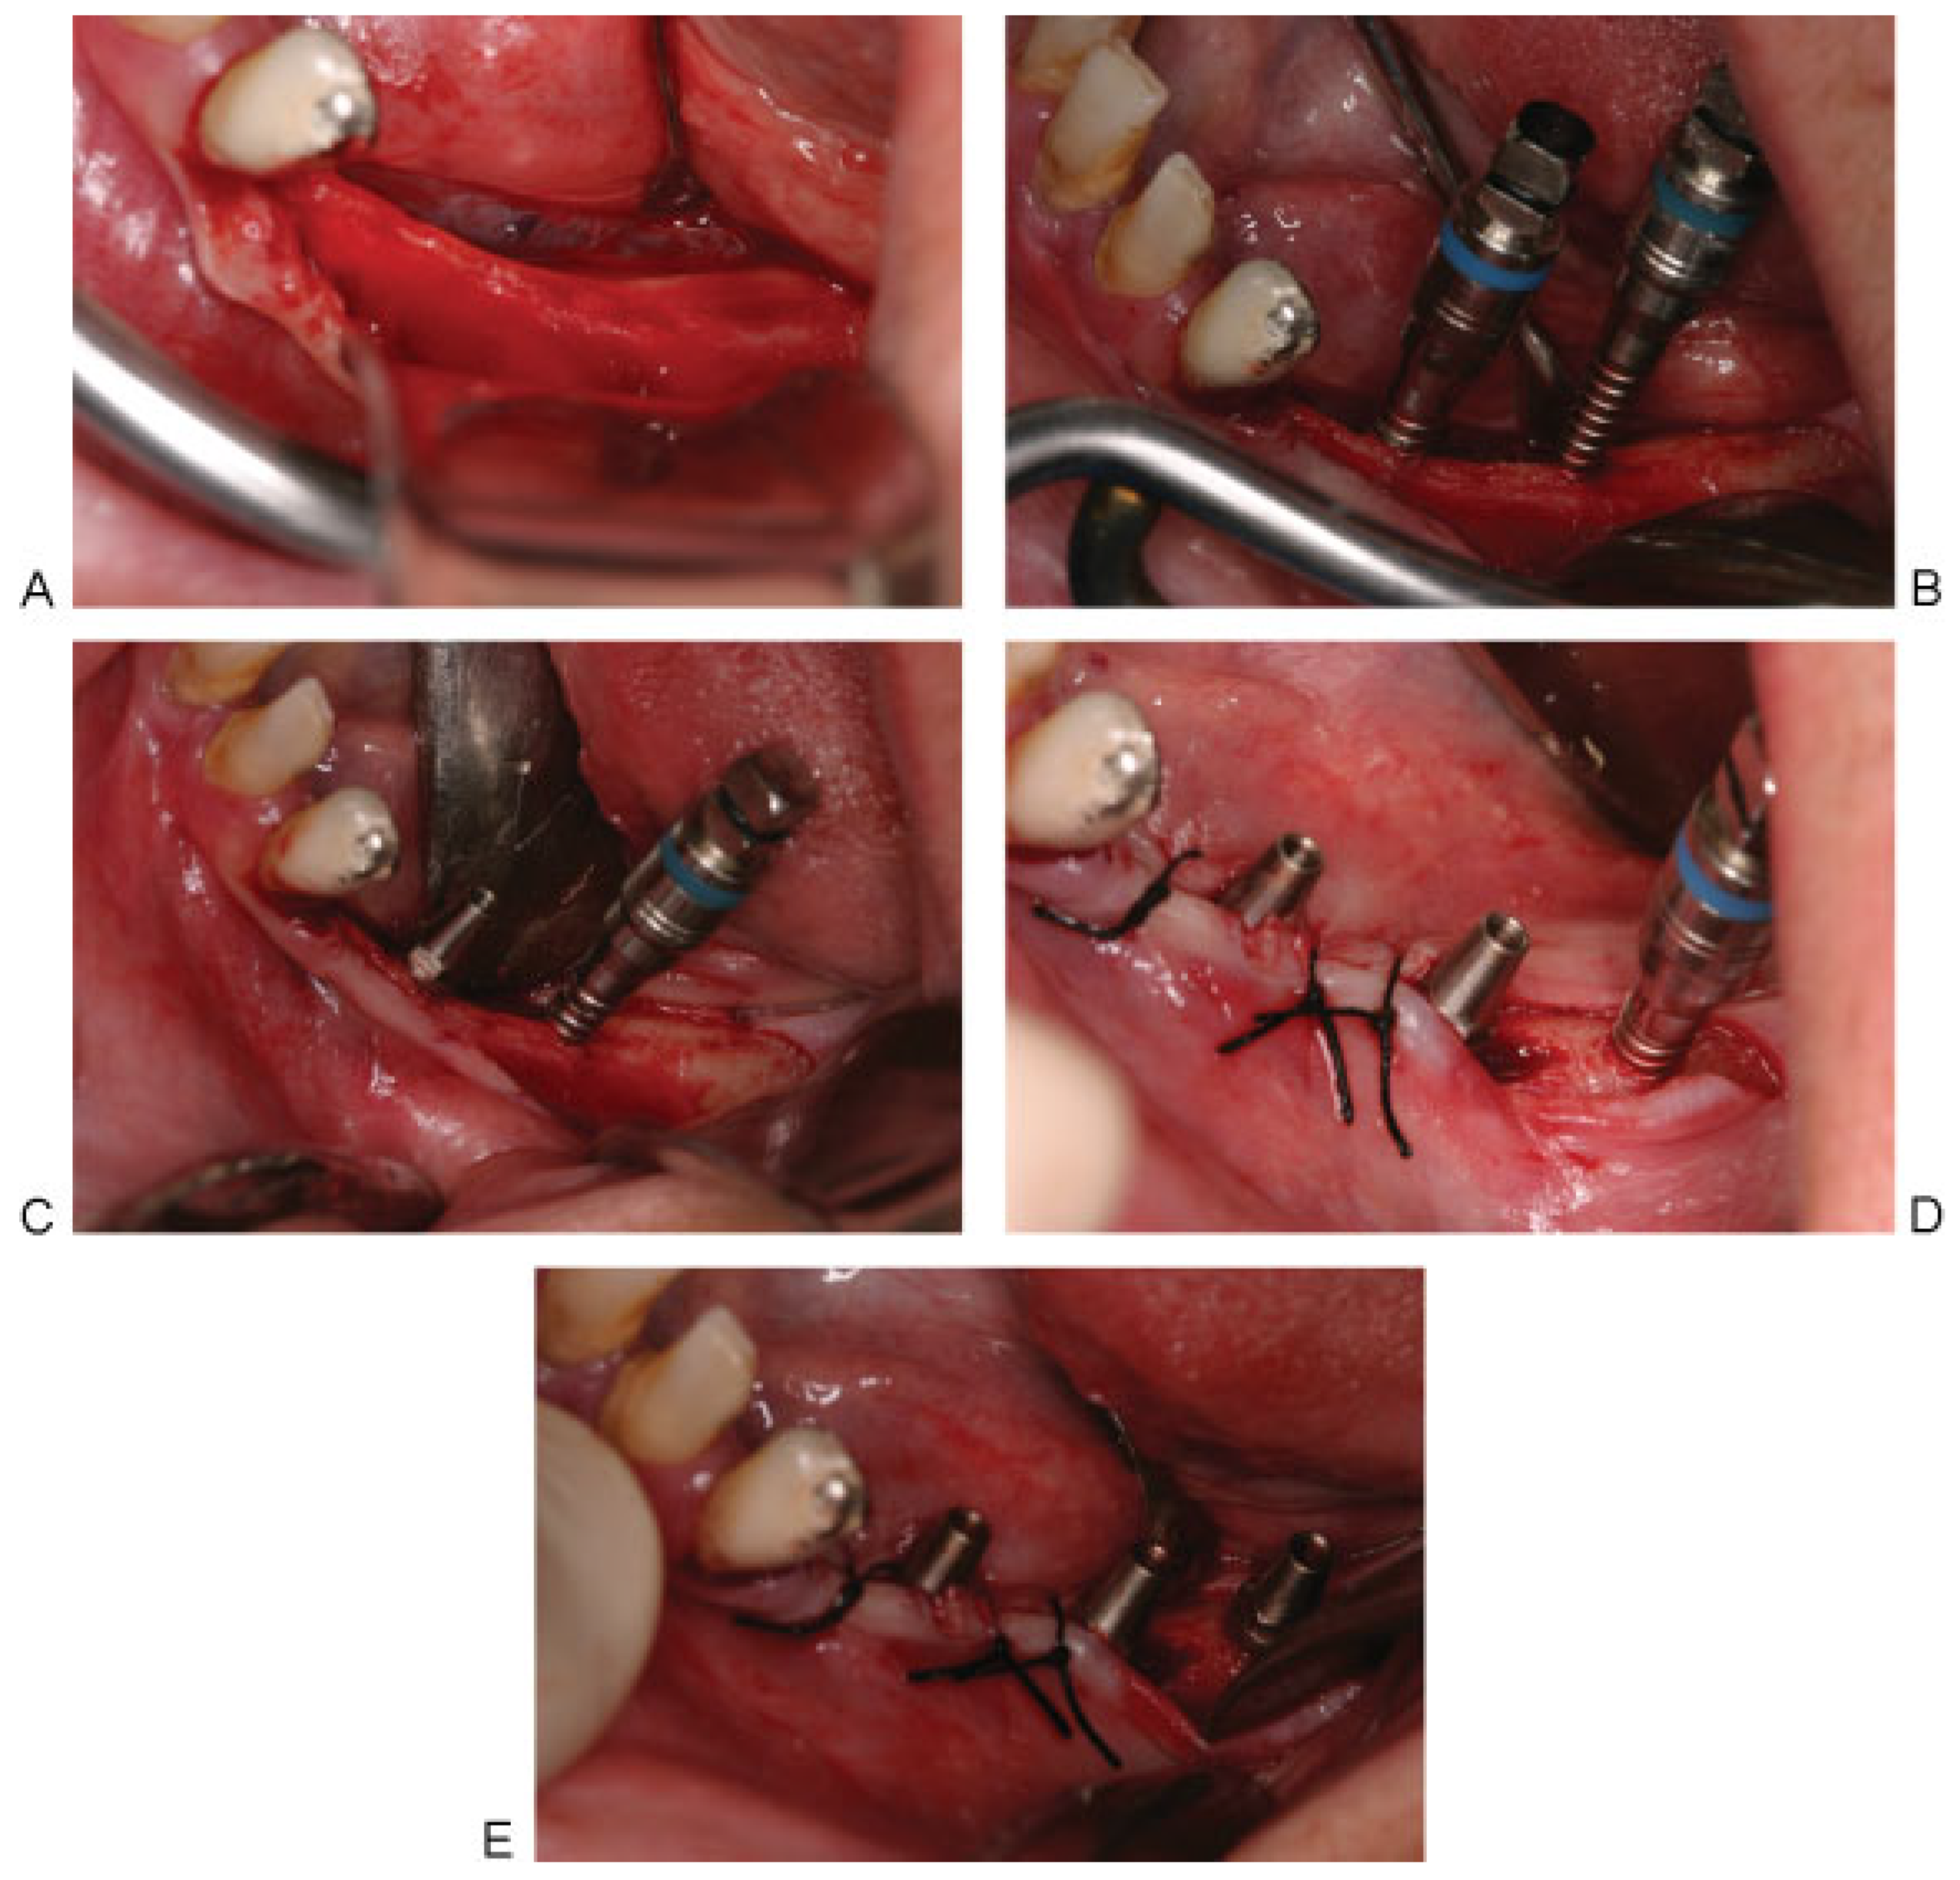

The corticotomy was performed in the premolars and first molar area lingual to the crest of the alveolar ridge, using the osteotomy inserts of NSK VarioSurg (NSK, Eschborn, Hesse, Germany), increasing the depth slowly and gradually until it reaches the inferior mandibular cortex. Threaded bone expanders (Microdent implants system, Barcelona, Spain) were then used sequentially to displace the buccal wall, containing the neurovascular bundle, buccally without injuring the nerve, thus atraumatically lateralizing the IAN away from the lingual wall. The expanders also served to prepare the implant bed manually avoiding heat generation by the use of drills. Both the right and left sides received two one-piece implants of 3.85-mm width, 12- and 14-mm length (MRT implants, Microdent implants system, Barcelona, Spain).They were threaded in place with a torque of 40 Ncm. On the left side, in the second molar area distal to the two implants, the pilot drill was used to perform an osteotomy. Bone expanders were used to allow for bone condensation and insertion of another 3.85-mm width, 14-mm length MRT implant. The implant engaged the inferior mandibular border aiming toward a tricortical anchorage (buccal, lingual, and inferior) for greater implant stability. The mucoperiosteal flaps were then sutured back using interrupted and horizontal mattress sutures (Figure 3 and Figure 4).

Figure 3. (A) Reflection of the mucoperiosteal flap on the left side and exposure of the alveolar bone, having a width of 2 mm in the premolars area, and 3 mm in the first molar area. (B) Threaded bone expanders no. 2 (color coded, blue) to allow for lateralization of the inferior alveolar nerve and expansion of the resorbed alveolar ridge. (C) The expanders must be maintained in place till the insertion of the implants to avoid collapse of the defect walls. (D) Insertion of two (MRT) implants in the premolars area and bone expander no. 2 in the second molar zone. (E) The three MRT implants in place and suturing back the flap.